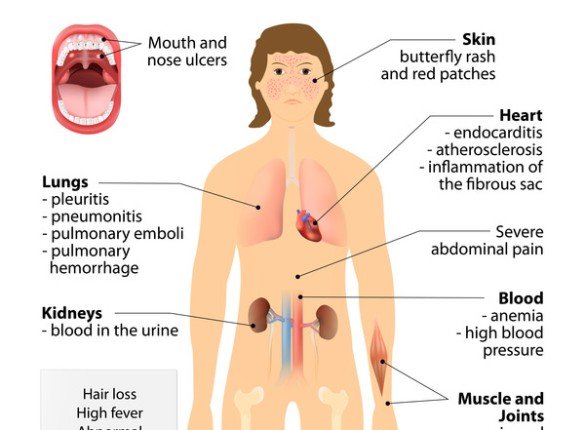

Psoriasis: Causes, Symptoms, Treatment

Psoriasis is a chronic skin condition th...